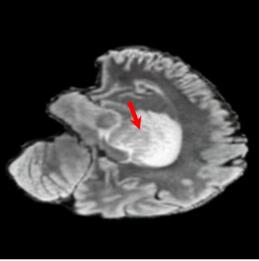

Tumour Information Preservation. For the brain tumor segmentation, we use a Swin UNETR model[27, 70], trained with random rotation, and intensity as data augmentation. In Figure 5, we highlight the tumor profiles of the generated MRIs compared to the ground truth tumour profile. In the test set with human ground-truth annotations (), the real MRI Dice score is 85.15 while the generated MRIs from a single slice have a dice score of 83.09. This shows how the generated MRIs indeed preserve the tumor information and can act as an affordable and informative pseudo-MRI, before conducting an actual costly MRI examination in hospitals.

B.4 Tumour Information Preservation

On the test set with human ground-truth annotations (), the brain volumes generated from single slice input preserve the volume of the different tumour components (paired t-test, for all 3 classes) (see Table 3). The real MRI Dice scores are put for reference to our generated MRIs. X-Diffusion outperforms baselines TPDM [36] and ScoreMRI [18] in tumour preservation (see Table 3 and Figure 12). We ran experiments comparing the tumour segmentation Dice Score varying X-Diffusion configurations. The multi-slice input X-Diffusion achieves a marginally better Dice Score than the single-slice input model (83.47 83.09). We also ran experiments with slice input used for volume reconstruction intersecting or not with tumour. We observe on average a drop of 6% Dice Score (see Table 3). Further away from the tumour the input slice for volume reconstruction is selected, and we observe a linear decrease in tumour segmentation Dice Score with the lowest value of 77.21 Dice Score (see Figure 15).

This shows how the generated MRIs indeed preserve the tumour information and can act as an affordable and informative pseudo-MRI, before conducting an actual costly MRI examination in hospitals. Given that our model has been trained on brain scans all with tumours, we expect to see hallucinations of tumours in healthy scans. We report two cases of failure of our model in Figure 16. Hallucinations of tumours on healthy samples represent 2% of the test set.